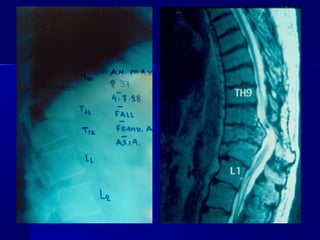

IInn ccaassee ooff sseevveerree nneeuurroollooggiiccaall

ddeeffiicciitt((FFrraannkkeell--AA..SS..II..AA:: AA--BB--CC))

Short

Stabilization